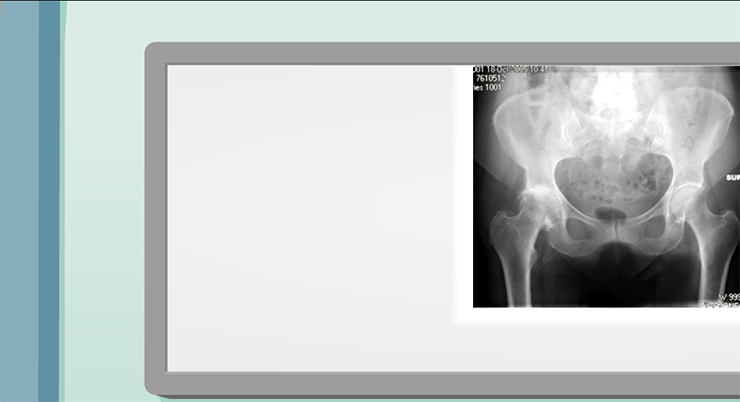

The worn, or sclerotic, bone at the top of the cup is harder to ream than the bone at the bottom.

The patient complained of more pain in the top part of the hip.

The hip bones compensate for excessive wear by growing osteophytes.